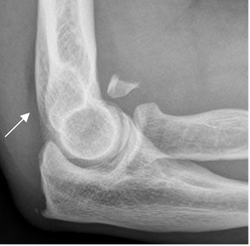

Fig 28 A. Fractura de la cabeza del radio.

Rx lateral, con visualización del cojinete graso posterior.

Fig 28 B. Fractura de la cabeza del radio.

A: Rx lateral. Signos de hemartrosis, con visualización del cojinete graso anterior (Flecha delgada) y posterior (Flecha gruesa). Con estos hallazgos, debe sospecharse la presencia de fractura.

B: Rx oblicua. Pequeña fractura desplazada en la cabeza del radio, responsable de la hemartrosis.